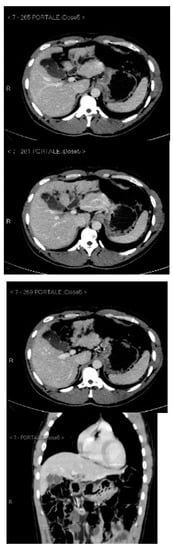

Subsequently, an upper-abdomen Computed Tomography (CT) scan and liver Magnetic Resonance Imaging (MRI) were performed (Figure 1, Figure 2, Figure 3, Figure 4, Figure 5, Figure 6 and Figure 7).

Figure 2.

CT portal phase.

Figure 3.

CT delayed phase.

A mass of 1.8 cm was detected within the biliary branch for the third hepatic segment, characterized by nodular impregnation in the arterial phase and irregular and partial washout in the portal venous phase. These findings were compatible with a heterologous lesion, although it was not possible to perform a diagnosis among HCC, intrahepatic CCA or other pathological lesions.